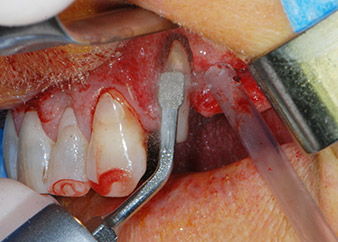

Bone deficiencies around the implants, at the mesial aspect of tooth 27 and around the buccal root of tooth 24, were filled with xenogeneic bone substitute particles and covered with an absorbable collagen membrane (Bio-Gide, Geistlich Biomaterials) for GBR augmentation (Figs. 13 and 14).

Xenogeneic bone substitute material

Fig. 13: Xenogeneic bone substitute material was used to fill the remaining osseous defects …

absorbable collagen membrane

Fig. 14: ... which was then covered with an absorbable collagen membrane. The grayish-pink structure between the elevators at the top margin of the picture represents interproximal papillary tissue.